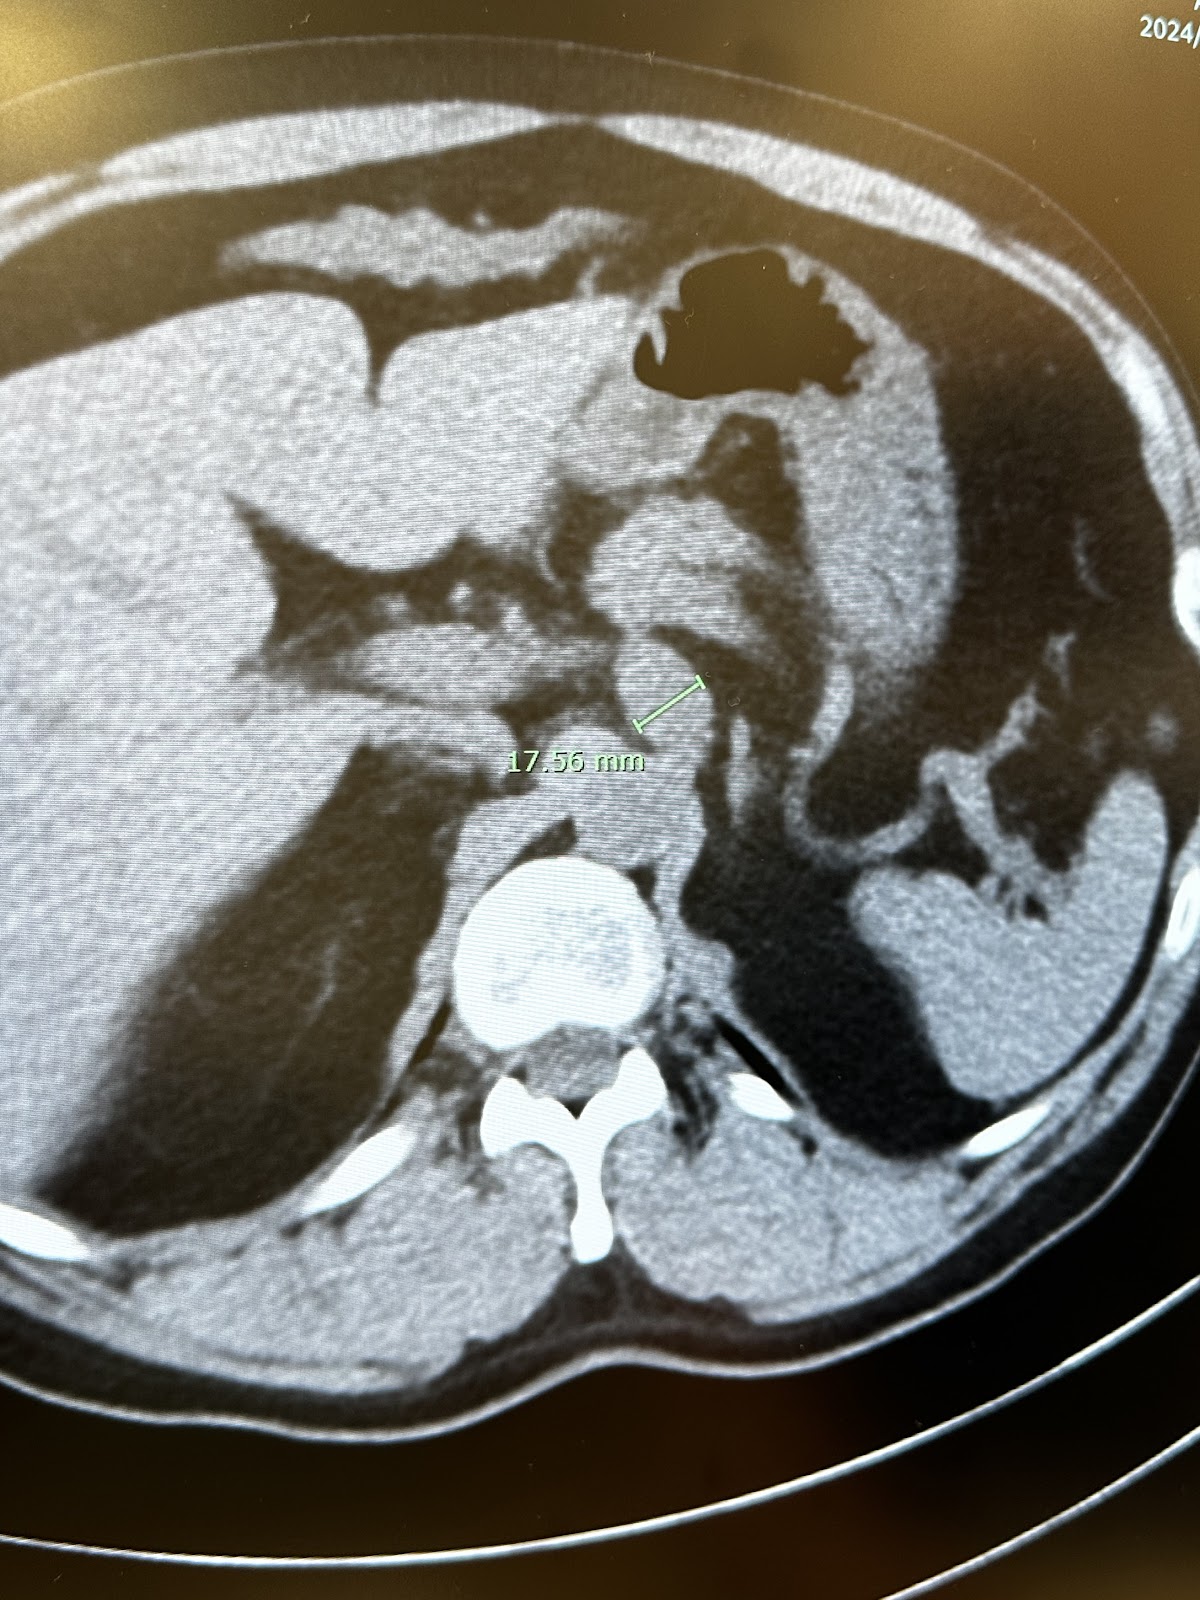

今日は検査結果を聞きに横浜市大病院に来ました。結果は動脈瘤に変化なし。1.8センチから数ミリも動いていませんでした。

残念ながら無罪放免にはならず、先生から「5年かけて大きくなってゆくものもあり予断できない。検査は続けなさい。」と言われ、2025年10月の予約を入れられてしまいました。